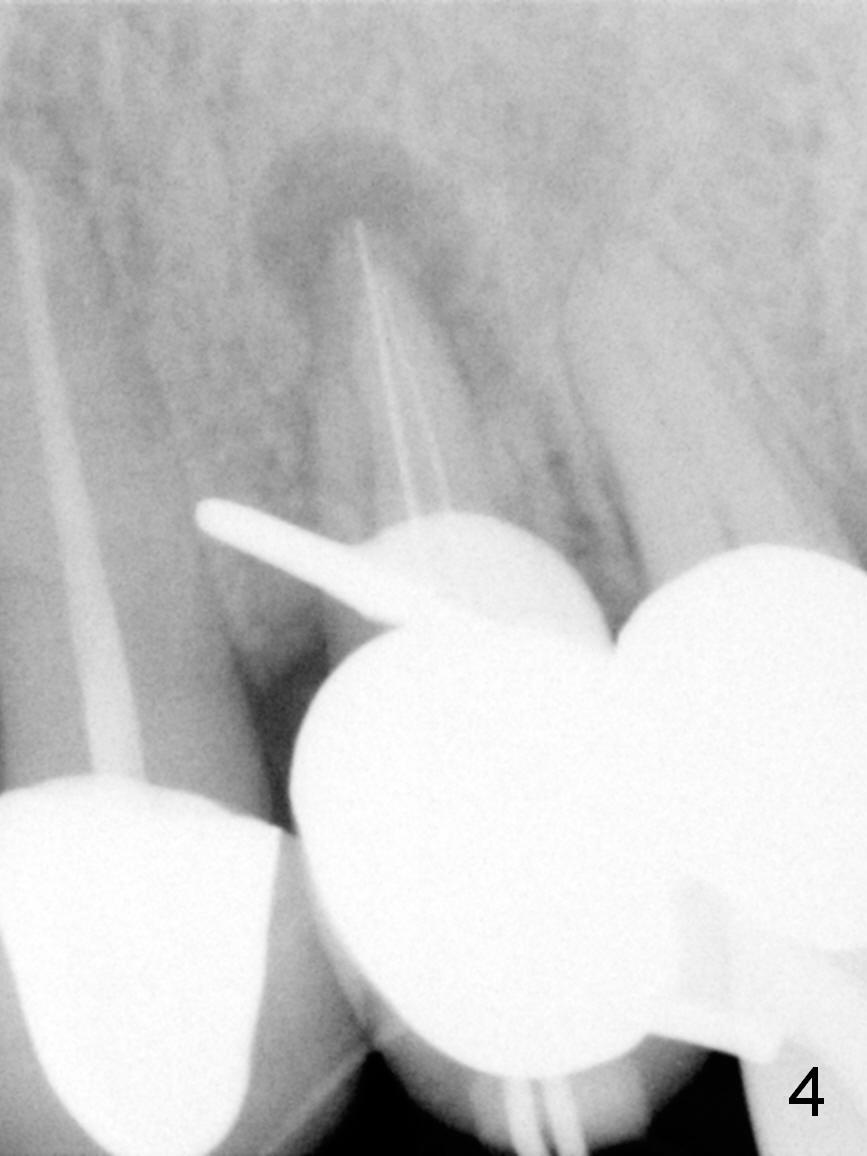

A 43-year-old woman has a persistent, asymptomatic fistula buccal to the tooth #12 (Fig.1,2). Prior to treatment, a #30 gutta percha is inserted into the fistula to confirm diagnosis (Fig.3). Hand files #15 and 20 are inserted to the buccal and lingual canals at 18 mm, respectively (Fig.4). Master cones (30/.04) are inserted buccally and lingually for 18 and 17 mm, respectively (Fig.5). There is minimal paste leakage after finishing RCT (Fig.6). Out of curiosity, the fistula is immediately curetted with removal of 2 small pieces of apparently leaked paste with minimal discomfort (total anesthetic: Xylocaine 34 mg, Epi 17 mcg). The fistula is expected to heal in 2 weeks.